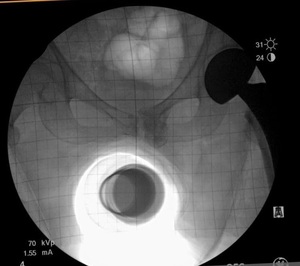

Multiple surgical approaches have been described for hip hemiarthroplasty (HHA) in the setting of a displaced femoral neck fracture.9 The direct anterior approach utilizes the intermuscular and internervous plane between the sartorius (i.e., hip flexor in the anterior thigh innervated by the femoral nerve) and tensor fascia latae (i.e., hip abductor innervated by the superior gluteal nerve) superficially, and the rectus femoris (i.e., hip flexor and knee extensor in the anterior thigh innervated by the femoral nerve) and gluteus medius (i.e., hip abductor innervated by the superior gluteal nerve) for the deep layer.10 This approach is typically performed in the supine position, which allows the use of intraoperative fluoroscopy, and in our study, a grid to measure and assess implant positioning, monitoring for leg length discrepancies (LLD) and femoral offset (FO) (Figure 1a). In contrast, the anterolateral approach utilizes the intermuscular plane between the tensor fascia latae and gluteus medius. The patient is positioned on a non-radiolucent peg board in the lateral position, which does not allow for utilization of a fluoroscopic grid.

At our institution, both surgeons each have their own technique, which has remained unchanged over the last eight years. One surgeon, using the GF technique, performs a supine, direct anterior approach with intraoperative fluoroscopic imaging utilizing a grid to view the internal components and to estimate the leg length and offset compared to the contralateral extremity (Figure 1a). The other surgeon, using the IE technique, uses an anterolateral approach with no intraoperative imaging. In order to reestablish neck length, the surgeon judges the length by visualizing and attempting to replace the amount of bone that was removed above the lesser trochanter (i.e., a bony anatomic landmark located near the hip). To restore offset, a manual intraoperative abductor shuck test is performed. For this test, the size of the femoral head is measured and used as a guide for the trial size for testing. After the hip hemiarthroplasty trial is reduced, soft tissue tension is manually assessed. Next, the surgeon applies a distracting force with a bone hook around the neck of the implant to check for overall fit and suction within the acetabulum (i.e., the socket of the hipbone where the head of the femur fits) (Figure 2). The soft tissue tensioning of the surrounding hip musculature is judged by whether the abductor musculature can be repaired without excessive tensioning. Leg length is again reassessed intra-operatively by comparing the medial malleoli (i.e., the inner side of the ankle) and patella (i.e., the small bone located in the front of the knee joint) of each leg.